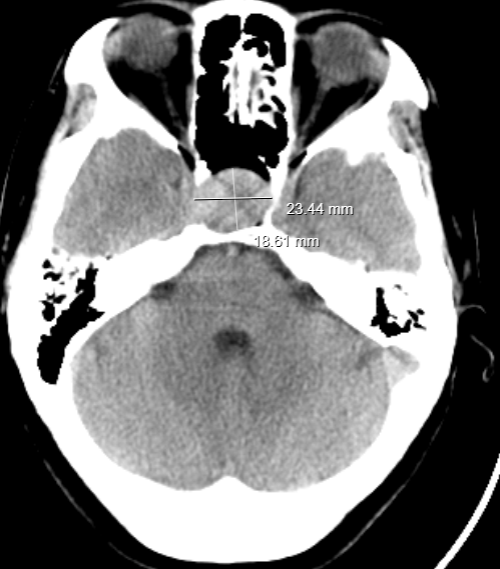

患者女性,50岁,因“头昏、视物不清2年,加重10+天”入院。入院完善头部X线计算机体层(CT)平扫:蝶鞍扩大并其内占位灶,建议MRI平扫+动态增强检查。双侧上颌窦及左侧筛窦炎。进一步完善垂体MRI平扫+增强:蝶鞍区扩大,垂体窝内见斑片状等T1、等稍短T2信号,形态欠规则,冠状位示病灶呈“雪人征”,测量其大小约26mm×27mm,垂体柄显示不清晰,视交叉受压上抬移位,鞍底塌陷,增强扫描可见病灶轻度强化,强化尚均匀。考虑垂体大腺瘤,建议结合病理检查。

术前头颅CT